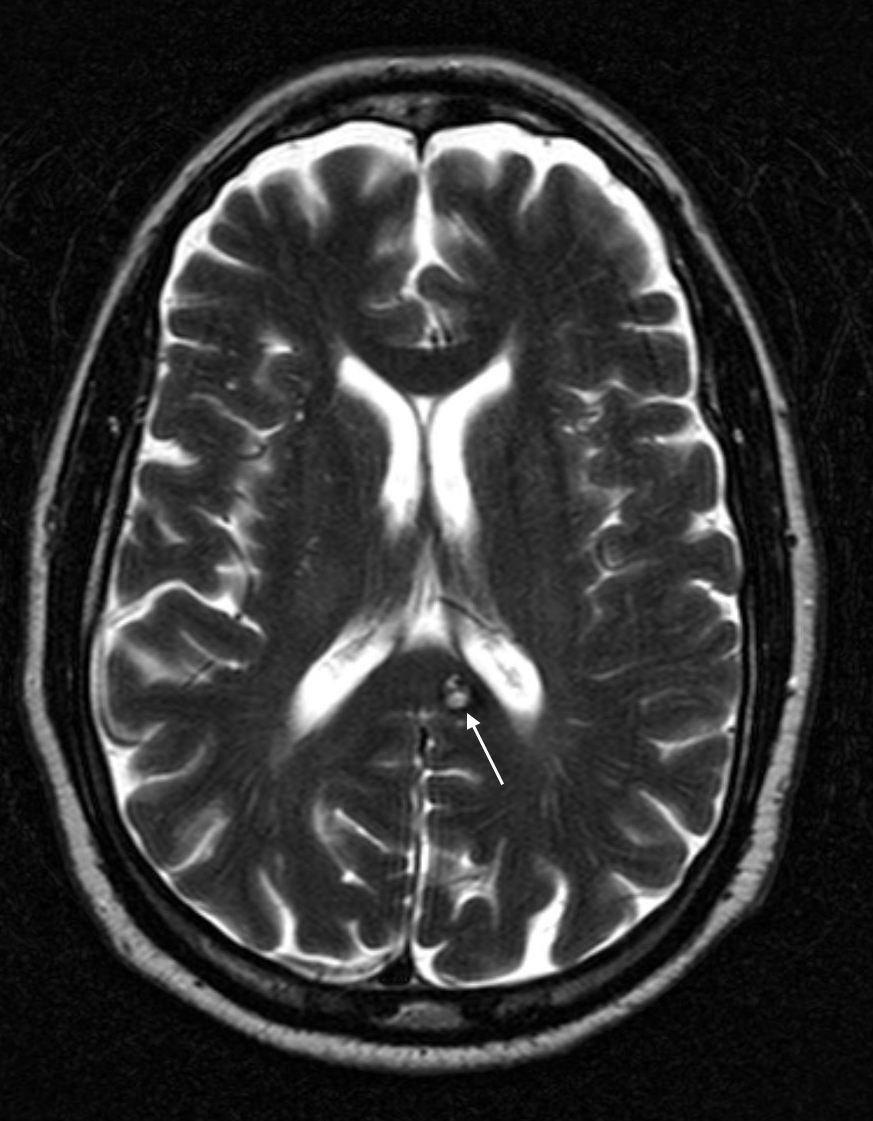

MAGNETIC RESONANCE IMAGING: T2 WEIGHTED HEAD MRI

Key features of the appearance of cerebral cavernous malformation on this imaging modality are:

- Classic “popcorn” or “berry” shape/appearance can be best appreciated on T2 weighted images.

- T2 bright: the lesions are typically bright on T2 weighted imaging.

- Dark ring artifact surrounding the lesion is typically seen on T2 weighted imaging.

Click on the thumbnails below to see examples of this condition utilizing this imaging modality: